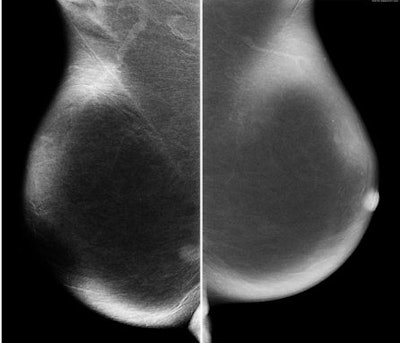

![]() |

| Same view on MRI. |